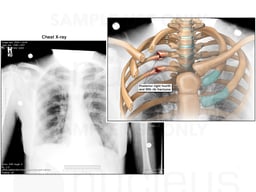

Right Rib Fractures

Image

exh78221b